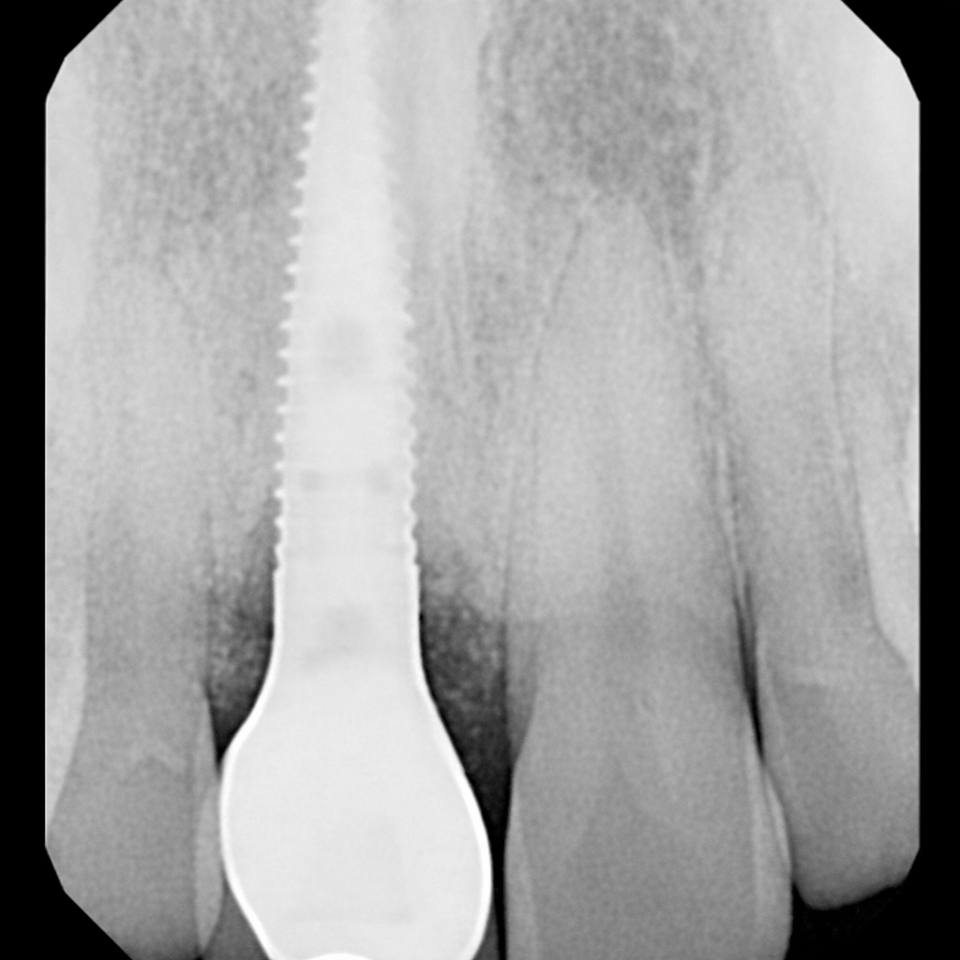

At Elite Dental Group, we provided emergency care that included root canal treatment on the upper central incisors. Dr. Satish Palayam performed an immediate implant placement for the right lateral incisor and completed a crown lengthening procedure on the palatal side of the right central incisor to support proper restoration. A provisional bridge was then placed to maintain both function and esthetics throughout the healing phase.

After a four month healing period, the final crowns were placed on the central incisors, and the implant for the right lateral incisor was successfully restored and finalized.